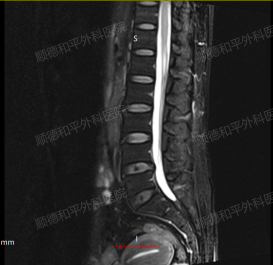

辅助检查:腰椎磁共振是重要的检查手段,可清晰显示椎间盘变性、膨出或突出,以及是否压迫硬脊膜囊、椎管、侧隐窝及椎间孔等。李女士的腰椎磁共振显示L4/5、L5/S1椎间盘存在变性、膨出并突出,且有相应的压迫情况,为诊断提供了有力依据。

术前&术后